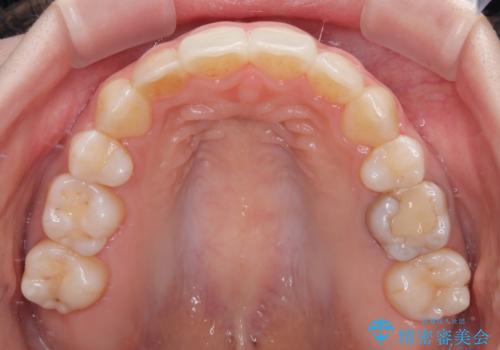

舌の突出癖が原因で後戻りをしたため、舌のトレーニングをしっかりと行っていただき、口元の突出感を改善することができました。

インビザラインの装着時間が守れず、1年強で終わる予定でしたが、4年間を要することとなりました。